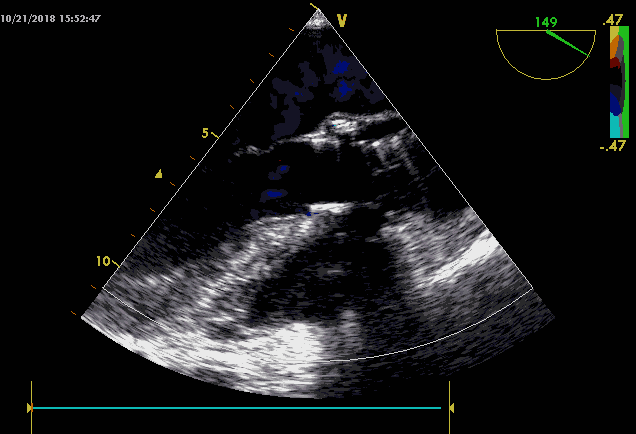

10.术后心超提示瓣膜形态可,少量瓣周漏;

1月后患者来我院随访,精神状态佳,活动自如,无气促,无胸闷等不适,之前的心衰症状完全消失。复查心超提示心功能恢复良好,无明显跨瓣压差,无明显瓣周漏。